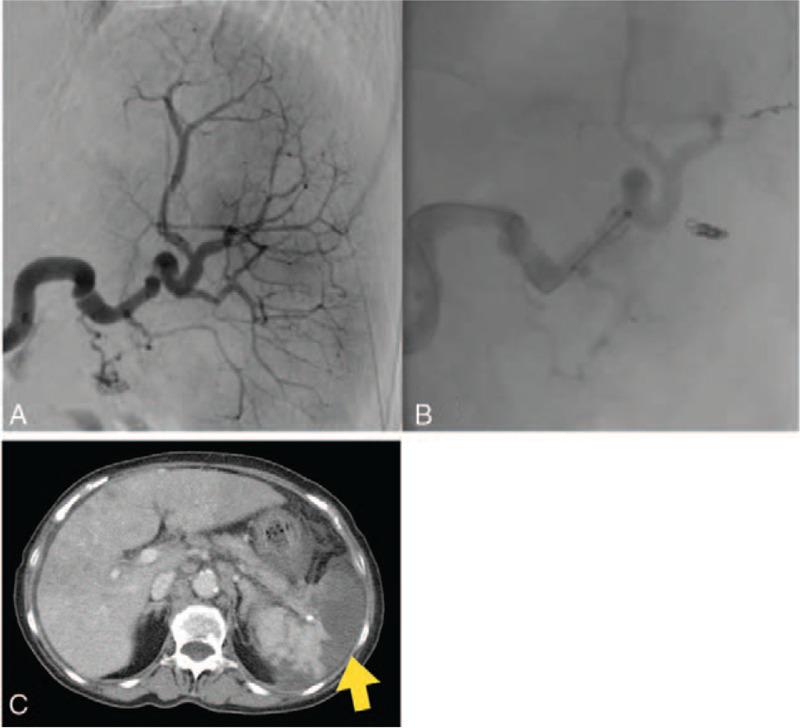

Hypersplenism causes thrombocytopenia, which may lead to the reduction or discontinuation of chemotherapy. Partial splenic embolization (PSE) is an effective treatment for thrombocytopenia associated with hypersplenism. However, there have been no reports of patients with gastric cancer who have resumed and continued chemotherapy after PSE for splenic hypersplenism associated with tumor infiltration.Here, we report two cases in which we performed PSE for hypersplenism associated with gastric cancer that had invaded the splenic vein. Chemotherapy was continued in both cases.

Upper gastrointestinal endoscopy and computed tomography showed advanced gastric cancer with invasion of the splenic vein and splenomegaly. Both patients developed thrombocytopenia.

Patients were treated with PSE.

PSE produced an increase in thrombocyte count, and chemotherapy could be resumed.